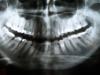

Тати Опубликовано 19 октября, 2009 Поделиться Опубликовано 19 октября, 2009 Здравствуйте, уважаемые доктора! У меня вот какая проблема – после перенесенного артрита рот не открывается полностью. В принципе, воспалительный процесс уже у мен прекратился (или так сильно замедлился), боли ушли, но и рот нормально пока не открывается. Уверена, что в ближайшем будущем (год-два) эту проблему я решу, т.к. есть надежда – была на консультации в ЦНИИСе, там предварительно (делали снимок ВНЧС) поставили фиброзный анкилоз ВНЧС. Сказали, что патология не такая уж сильная, в операции нет смысла и велели разрабатывать челюсть, работать на открывание рта. Стараюсь изо всех сил, пасть разеваю, как крокодил )! Но у меня, к сожалению, есть оперативная проблема, не терпящая отлагательства. Две недели назад возник пульпит, пошла к стоматологу. В результате поиска пульпитного зуба два из них - 6-ой и 7-ой слева внизу - были депульпированы. Врач сказал, что при таком доступе нет возможности пролечить как следует каналы и запломбировать, наложил мумифицирующую пасту. Пока хожу с временной пломбой над этой пастой, но нужно как-то кардинально решать проблему! Мне очень бы хотелось ХОРОШО вылечить эти зубы. Финансы не напрягают. Что можно посоветовать в этой ситуации? 1) Есть ли шанс нормально пролечить каналы? 2) Может быть, есть какое-то специальное оборудование для помощи таким, как я. Вот, например, лазарные стоматологические установки – для работы с ними рот надо так же сильно открывать или мой вариант годится? 3) Мне бы хотелось отремонтировать зубы так, чтобы забыть о них лет на 20, как минимум. Может, поставить золотоплатиновые вкладки ? Ставят ли их на непролеченные каналы и чем это грозит? 4) Если поставить золотоплатиновые вкладки + такие же коронки, то как обтачиваются зубы под них? В моем случае каков риск задеть соседние зубы (они у меня очень плотно друг к другу). Я работаю изо всех сил над открываем рта, и в общем дело продвигается, только медленно. Сустав разработать – это не ешака купить! Хожу с мумифицирующей пастой и временной пломбой уже две недели, так что время, к сожалению, не терпит. В общем, я буду рада любому профессиональному мнению по этому поводу. Заранее огромное спасибо. Прилагаю два снимка – Ортопантомограмму и фото моего максимально открытого рта. Ссылка на комментарий

x3m Опубликовано 19 октября, 2009 Поделиться Опубликовано 19 октября, 2009 Снимок не очень четкий. Но по вопросам можно ответить:1. да2. лазер - это не оттуда немного. Вам надо лечить каналы. Расширяются и чистятся они металлическими инструментами, промываются растворами. И пломбируются пастой и гуттаперчей.3. забыть о зубах - зависит от качества восстановления. о стоматологе совсем забыть не получится - раз в полгода - на осмотр как на праздник на непролеченные каналы - не ставится. вкладки фиксируются в каналах, которые должны быть запломбированы до верхушек корней.4. обтачиваются на толщину коронки. Риска задеть соседей - никакого (если врач умеет правильно обработать зуб под коронку).Разрабатывать надо.Ждать нет смысла. Надо пойти к эндодонту, делать анестезию и лечить каналы как надо. ЗЫ.имхо, (судя по обзорному снимку) лечению подлежат:7,6,5 зубы справа вверху.7,8 зубы слева вверху.5,8 зубы слева внизу.5,6,7,8 зубы справа внизу.http://i050.radikal.ru/0910/83/def100e09dc2.jpg Ссылка на комментарий